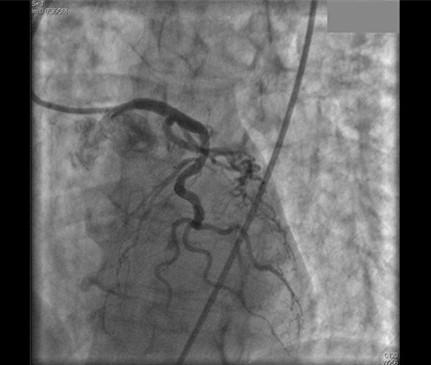

TCM的实际发生率尚不清楚,但该病可能占所有疑似急性心肌梗死病例的1%~2%。TCM患者一般表现为胸痛、心电图ST段抬高和心肌酶水平升高,与急性MI的表现是一致的。但当患者行冠状动脉血管造影术时,可发现无显著冠状动脉狭窄(如图所示),而左心室造影显示左心室心尖部存在球样扩张。

左图:服用多种药物自杀因药物毒性引发TCM的患者,冠脉血管造影正常。

右图:该患者的舒张期(上图)和收缩期(下图)左室血管造影显示心尖部运动减少。